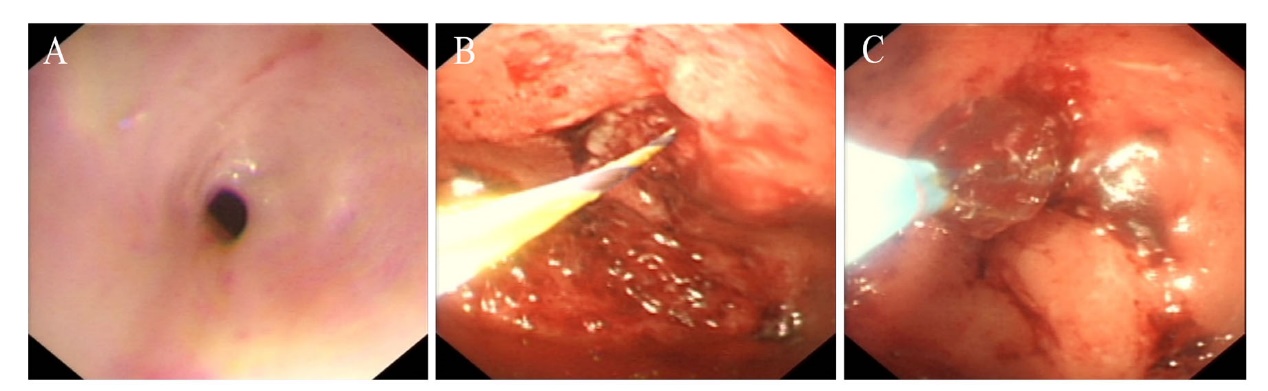

患者入院后于2021年8月24日行胃镜检查提示食管入口、食管中下段距门齿约30~40 cm处明显狭窄(图1A),予探条扩张后方能入镜至胃内,见胃窦变形,小弯侧大片溃疡形成,底覆白苔,周边黏膜充血水肿,幽门结构难以辨认(图1B),予球囊扩张(图1C),并放置鼻空肠管,术后第二天予肠内营养,但患者出现恶心、呕吐以及腹胀症状。2021年8月25日行上消化道碘剂造影显示食管上段、中下段狭窄,造影剂通过欠顺畅(图2);部分胃体、胃窦僵硬、狭窄并梗阻。心理科会诊提示患者有消极轻生念头,考虑为抑郁焦虑状态。经上述治疗后,患者肠内营养耐受情况欠佳,病情未见明显改善,梗阻仍然存在。经医务人员综合评估,确认该患者具有行PEG/J的适应证,无禁忌证。获得患方知情同意后,于2021年8月28日在气管插管全身麻醉下行PEG/J。患者取仰卧位,麻醉后经口插入胃镜,见食管仍狭窄,入镜至胃内,见胃腔变形,胃底较多胃液潴留,吸净后继续入镜至胃窦、幽门前区,见幽门仍狭窄,仔细辨认后送镜至十二指肠,见球部、降段黏膜光滑,退镜至胃体部,注气后于左上腹反复运用传统指压试验及透光试验寻找理想穿刺点,由于胃腔变形、胃移位,术者反复多次选点失败,后联合运用负压针吸试验,用含5 mL 生理盐水的注射器抽吸针筒保持负压,同时保证胃腔内充分注气,再次选定穿刺点后经腹部皮肤逐层缓慢穿刺至胃腔(图3A),最终定位于剑突下2 cm偏左约3 cm,消毒铺巾后,采用牵拉法完成胃造瘘术,并经胃造瘘管(管径6 mm)送入小肠管(管径3 mm)至空肠上段(图3B[5]。患者术中、术后生命体征平稳。于术后6 h开始向小肠管内注入少量营养液并逐量增加至正常管饲量,后逐渐过渡至日常食糜。经处理,患者病情及营养状况逐渐好转,于2021年9月25日出院。1个月后患者遵嘱返院复诊,监测体质量由住院期间最轻时39 kg增至47 kg,复查碘剂造影示食管上段狭窄较前减轻,中下段食管狭窄;胃窦部至幽门区明显狭窄伴梗阻,仅见少许造影剂通过幽门。医师与患方保持电话随访至撰稿日,得知患者呕吐次数逐渐减少至缓解,营养状况持续改善,造瘘管固定良好,造瘘口无红肿、渗液等(图3C)。

图2 一例上消化道严重腐蚀伤患者的上消化道碘剂造影图片

注:A为上消化道碘剂造影正位;B为上消化道碘剂造影斜位;箭头所示为食管上段、中下段狭窄处。